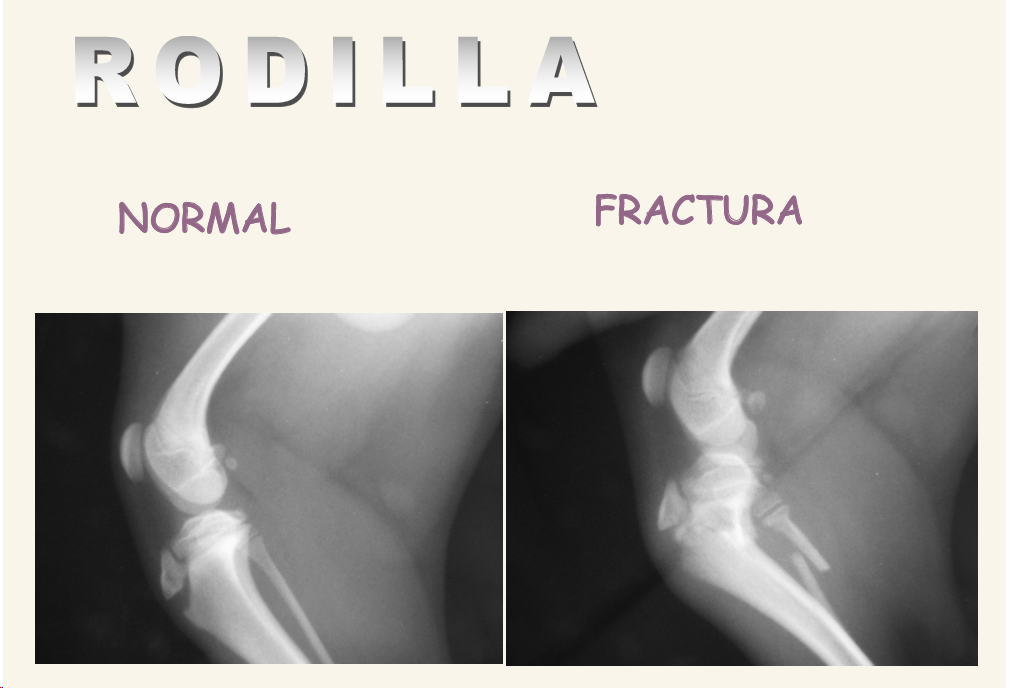

Rodilla

Proyecciones Media-Lateral y Caudo-Craneal o Craneal-Caudal con rodilla en posición neutra y cuña debajo del tarso para evitar rotación. Centrar en cóndilo femoral, en distal.

Hacer también proyecciones en estrés (ligamentos)

Cosas que podemos ver:

- Rotura del LCA o Ligamento cruzado anterior: TAMBIEN SE VE DERRAME ROTULIANO y desplazamiento de la tibia

- Fracturas

- En cachorros muy comun las fracturas de rodilla en lineas de crecimiento en la meseta tibial

Enfermedad degenerativa articular o DEA

- Por inestabilidad o secundaria a traumatismos. Hay deformaiones congenitas o por artritis infeciosa o inmunomediada

- El primer signo radiológico es el derrame, se pierde radiolucidez en tejido entre articulaciones (Disminución de la almohadilla grasa subrotuliana) , se ve gris en vez de negro bajo la rótula